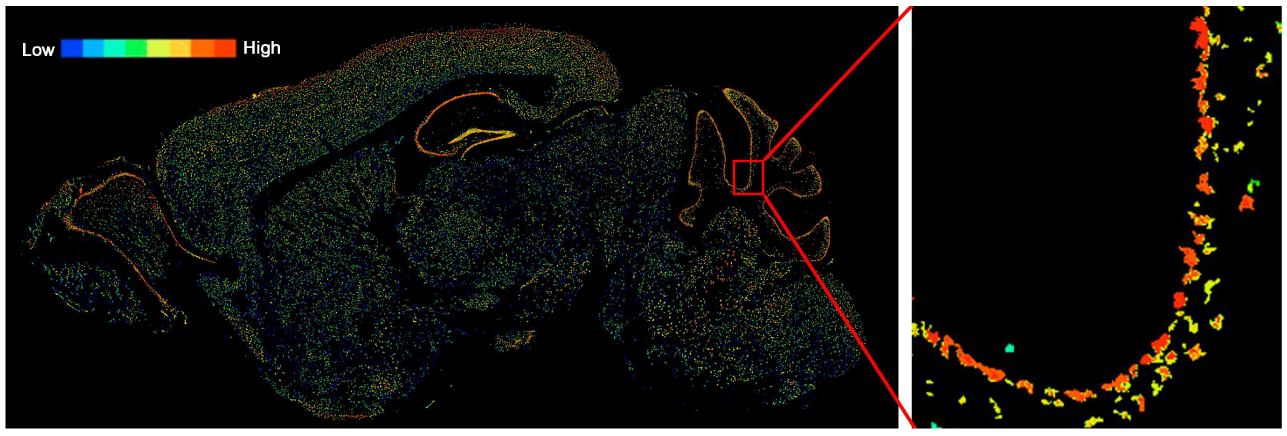

接下来,作者借助组织学和病理学分析发现,cKO小鼠的浦肯野细胞明显减少(图1D,E)。同时,平衡木行为学实验结果显示,浦肯野细胞数量与足部滑移呈负相关(图1F),这提示了小鼠运动协调性紊乱中存在Snx14依赖的浦肯野细胞变性。进一步,作者借助浦肯野细胞标记物碳酸碱酶8(carbonic anhydrase 8, CA8)进行免疫荧光染色,结果发现,Snx14f/f小鼠中约为16%的CA8阳性的浦肯野细胞轴索肿胀,透射电镜(TEM)观察发现,在这些肿胀的轴突中线粒体、溶酶体和其他细胞器出现异常积累(图1G-I)。

图1 SNX14缺陷导致小鼠运动协调性紊乱和浦肯野细胞变性